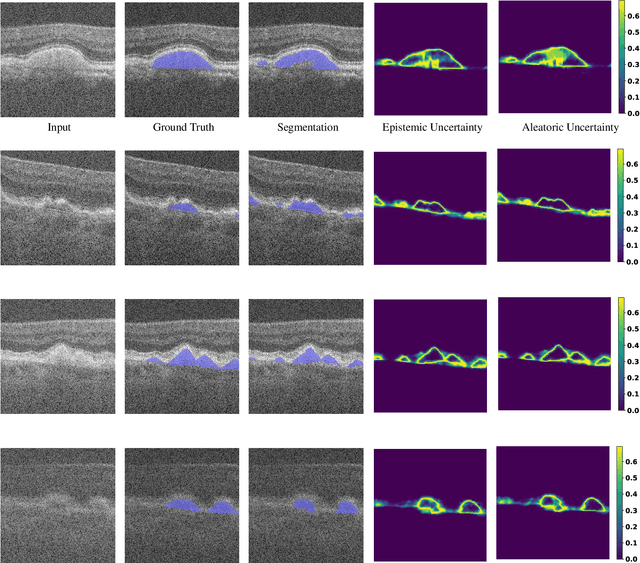

Abstract:Age-related macular degeneration (AMD) is one of the leading causes of permanent vision loss in people aged over 60 years. Accurate segmentation of biomarkers such as drusen that points to the early stages of AMD is crucial in preventing further vision impairment. However, segmenting drusen is extremely challenging due to their varied sizes and appearances, low contrast and noise resemblance. Most existing literature, therefore, have focused on size estimation of drusen using classification, leaving the challenge of accurate segmentation less tackled. Additionally, obtaining the pixel-wise annotations is extremely costly and such labels can often be noisy, suffering from inter-observer and intra-observer variability. Quantification of uncertainty associated with segmentation tasks offers principled measures to inspect the segmentation output. Realizing its utility in identifying erroneous segmentation and the potential applications in clinical decision making, here we develop a U-Net based drusen segmentation model and quantify the segmentation uncertainty. We investigate epistemic and aleatoric uncertainty capturing model confidence and data uncertainty respectively. We present segmentation results and show how uncertainty can help formulate robust evaluation strategies. We visually inspect the pixel-wise uncertainty and segmentation results on test images. We finally analyze the correlation between segmentation uncertainty and accuracy. Our results demonstrate the utility of leveraging uncertainties in developing and explaining segmentation models for medical image analysis.